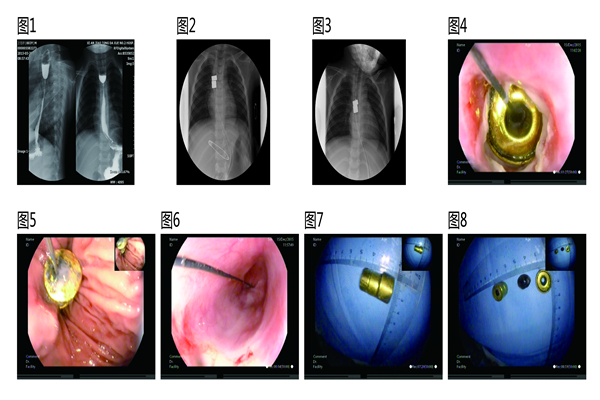

该患儿因误食烧碱后出现吞咽困难出现口腔、胸骨后疼痛,口腔充血糜烂,当地医院给予洗胃等处理,伤后3天食管镜检如常,其后开始进食,发现进食顺利;伤后半月起逐渐出现吞咽不畅,逐渐加重偶伴呕吐,诊断为食管狭窄。曾就诊于西安多家大型医院均因诊治难度大未给予明确诊治意见。之后慕名赴交大二附院消化内科董蕾教授处就诊,行内镜下食管球囊扩张治疗多次后反复出现吞咽困难,仅可进全流食。为指定详尽全面的诊治计划,联系并经小儿外科高亚教授同意后于2015年7月收住交大二附院小儿外科。入院后食管造影提示“食管主动脉弓处狭窄,仅残留直径为数毫米的孔洞”;CT及MRI检查提示“食管狭窄部位与主动脉弓分界不清”,初步诊断为食管化学性烧伤后瘢痕狭窄。科室讨论过程中,高亚教授指出该患儿具有手术治疗指征,但常规手术(食管狭窄段纵切横缝、狭窄段切除食管吻合术以及代食管手术)存在种种不足如食管狭窄段纵切横缝术为瘢痕愈合,术后可能发生吻合口漏,食管再狭窄可能性高、且难以扩张治疗,需行狭窄段切除吻合术或代食管手术;本例狭窄段位于食管中段,邻近主动脉弓和左主支气管,因碱性化学性烧伤可能引起食管全层损伤,导致食管与周围组织紧密粘连,贸然施行狭窄段切除食管吻合术手术操作有一定难度,狭窄段切除后如食管近、远端距离长,则无法吻合,或者因吻合口有张力,术后出现吻合口漏及食管再狭窄风险加大。除上述常规手术外,高亚教授复习文献,结合患儿实际病情指出采用食管磁压榨吻合术即内镜下将一块磁铁经口腔置入狭窄段上方食管内,将另一块磁铁经胃造口通过贲门置入狭窄段下方食管内,两块磁铁相互吸引,狭窄部可因磁铁的压迫缺血而致坏死脱落,食管壁增生愈合,从而恢复食管的连续性。完成吻合后磁铁可经肠道自行排出体外或通过内镜取出。此方法相当于食管缓慢扩张 + 食管延长 + 狭窄段切除食管吻合术,具有操作简便、微创的优点。术后亦存在再狭窄可能,但由于原狭窄段已经切除,新吻合口狭窄易于内镜扩张治疗。此外,我校吕毅教授团队有较成熟的成人磁压榨治疗经验,可提供相关技术支持。

告知并取得患儿家长同意并经过充分的术前准备、多次院内(校内、国内)多学科会诊、院内伦理审查、专门加工吻合器具后,在吕毅教授、董蕾教授团队的协助支持下,高亚教授团队于2015年11月26日率先在国内施行首例磁压榨吻合术治疗小儿食管狭窄,术中操作顺利,时间约60分钟,无手术并发症;术后2周内复查胸片提示磁环未发现磁环异位、扭转、成角、滑脱,且磁环间距逐渐缩小至不足1mm,胃镜检观察食管内磁环对合良好;术后第18天在内镜下借助抓钳的牵拉,磁环顺利脱落进入胃腔并在经导丝牵引下顺利自胃造瘘口处取出,胃镜下探查食管吻合处通畅,无明显狭窄,粘膜光滑无瘢痕形成,无明显渗、出血及食管破裂等。术后复诊间隔1月,来院随访至今共12月,术后间隔1月行食管扩张术、放置支架2次预防再狭窄,胃镜复查未见异常,患儿进食正常,经评估患儿身高、体重均在同龄儿平均水平之上。